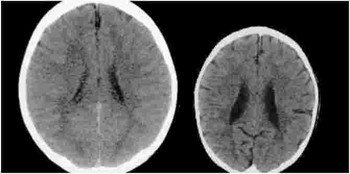

Look at the above image of 2 brains. They both belong to 3-year-old children. Why then, is the brain on the left much bigger than the one on the right?

If you see, the image on the left also has fewer spots, and far fewer dark “fuzzy” areas.

According to neurologists, the brain on the right lacks some of the most fundamental areas present in the brain on the left.

In Professor Bruce Perry’s words, “The CT scan on the left is an image from a healthy 3-year-old with an average head size. “

“The image on the right is from a 3-year-old child suffering from severe sensory-deprivation neglect. This child’s brain is significantly smaller than average and has enlarged ventricles and cortical atrophy.”